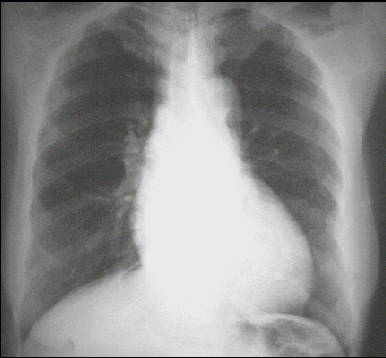

These chest X rays show left ventricular enlargement and a dilated aorta. The PA view demonstrates cardiomegaly, as evidenced by a cardiothoracic ratio greater than 50%. Note also the increased inferolateral cardiac border that is consistent with left ventricular enlargement due to volume overload. The ascending, transverse, and descending aortic shadows are also prominent.